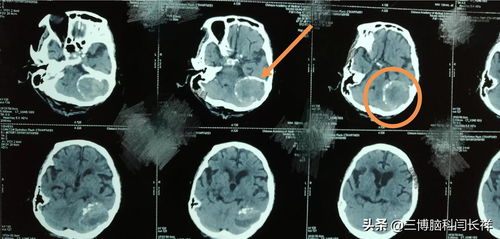

脑膜瘤影像学诊断及治疗

脑膜瘤的临床特点是发病缓、病程长。不同部位脑膜瘤可有不同的临床表现,因成年人发病较多,故成年人有慢性头痛、癫痫、一侧或两侧视力减退、共济失调等,特别是伴有进行性加重的颅内压增高症状时,要考虑脑膜瘤的可能性。通过做头部CT、核磁共振(MRI)或头部PET/CT,可对脑膜瘤早期确诊。

脑膜瘤属实质外生长的肿瘤,大多属良性。对脑膜瘤的治疗,以手术切除为主。原则上应争取完全切除,并切除受肿瘤侵犯的脑膜与骨质,以期根治。越早发现,越早手术,效果越好,风险越小。